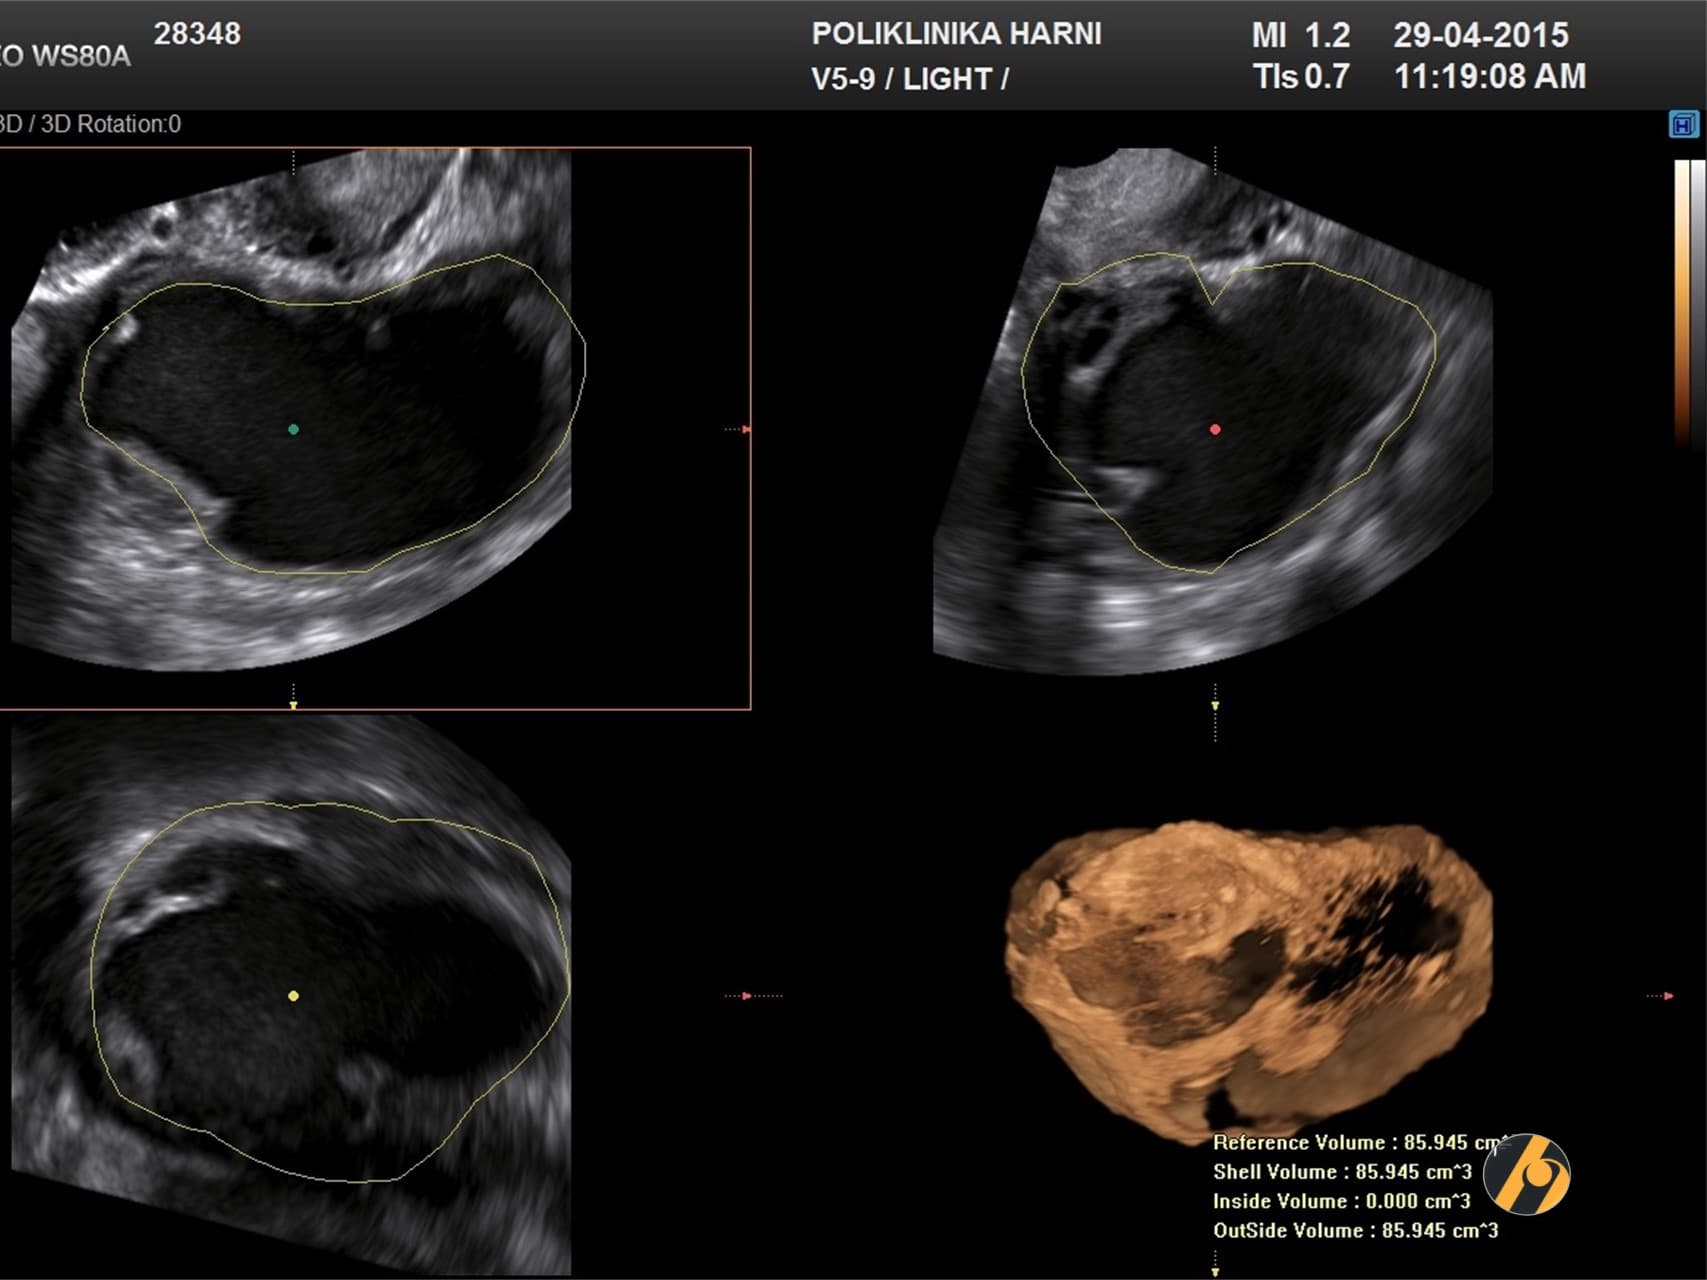

Premda su laparoskopija i patohistološka dijagnostika zlatni standard u dijagnostici endometrioze, u postavljanju dijagnoze od pomoći mogu biti i drugi manje invazivni postupci. Nažalost, ove tehnike kao što su transvaginalna sonografija i magnetska rezonancija nisu u stanju otkriti manje ili lezije koje su manje aktivne. Transvaginalna ultrazvučna dijagnostika učinkovito otkriva endometriotička žarišta čiji je promjer veći od 19 mm (¾ incha).